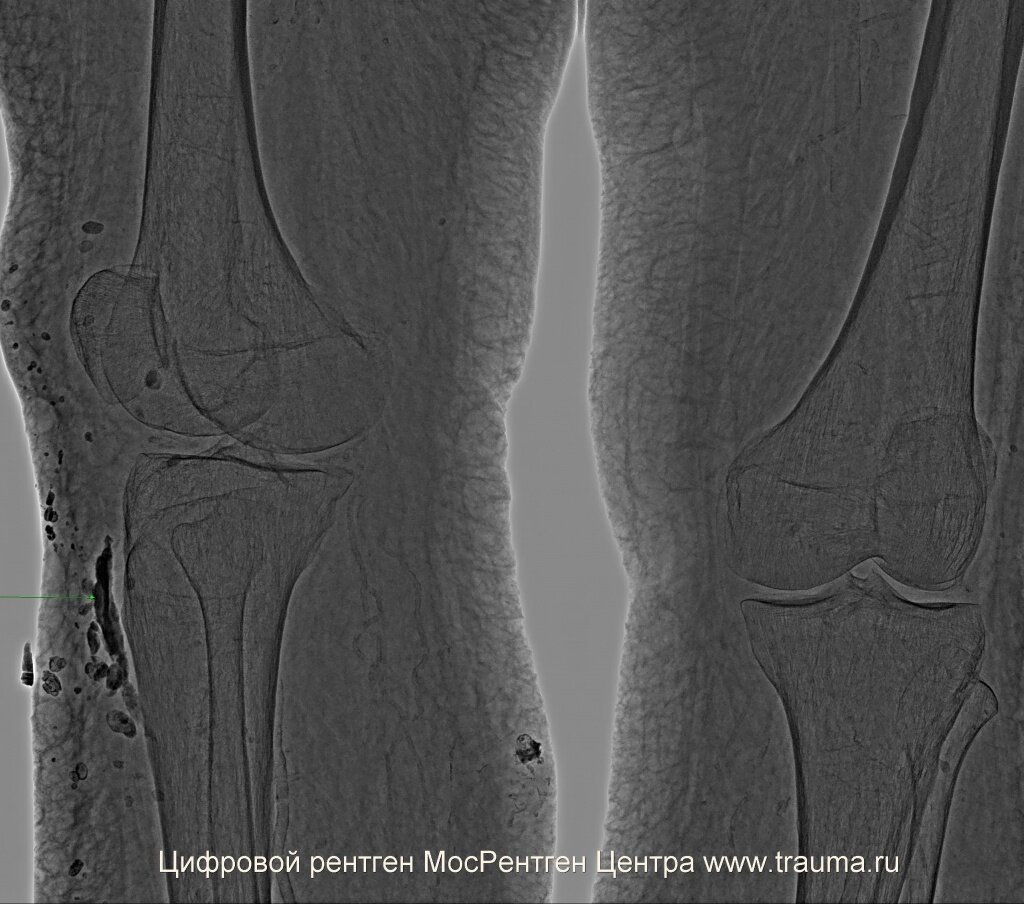

При сохранении сильной боли нужно проконсультироваться у травматолога и сделать рентгенограммы в двух проекциях для исключения перелома костей. Рентген позволяет определить, есть или нет перелом с вероятностью до 99%. Если есть подозрение на перелом, а рентген этого не определяет, можно выполнить компьютерную томографию с построением трехмерного объекта. При повреждении мягких тканей более эффективна магнитно-резонансная томография (МРТ). Какую методику более эффективно применить в каждом случае? Это решает врач.